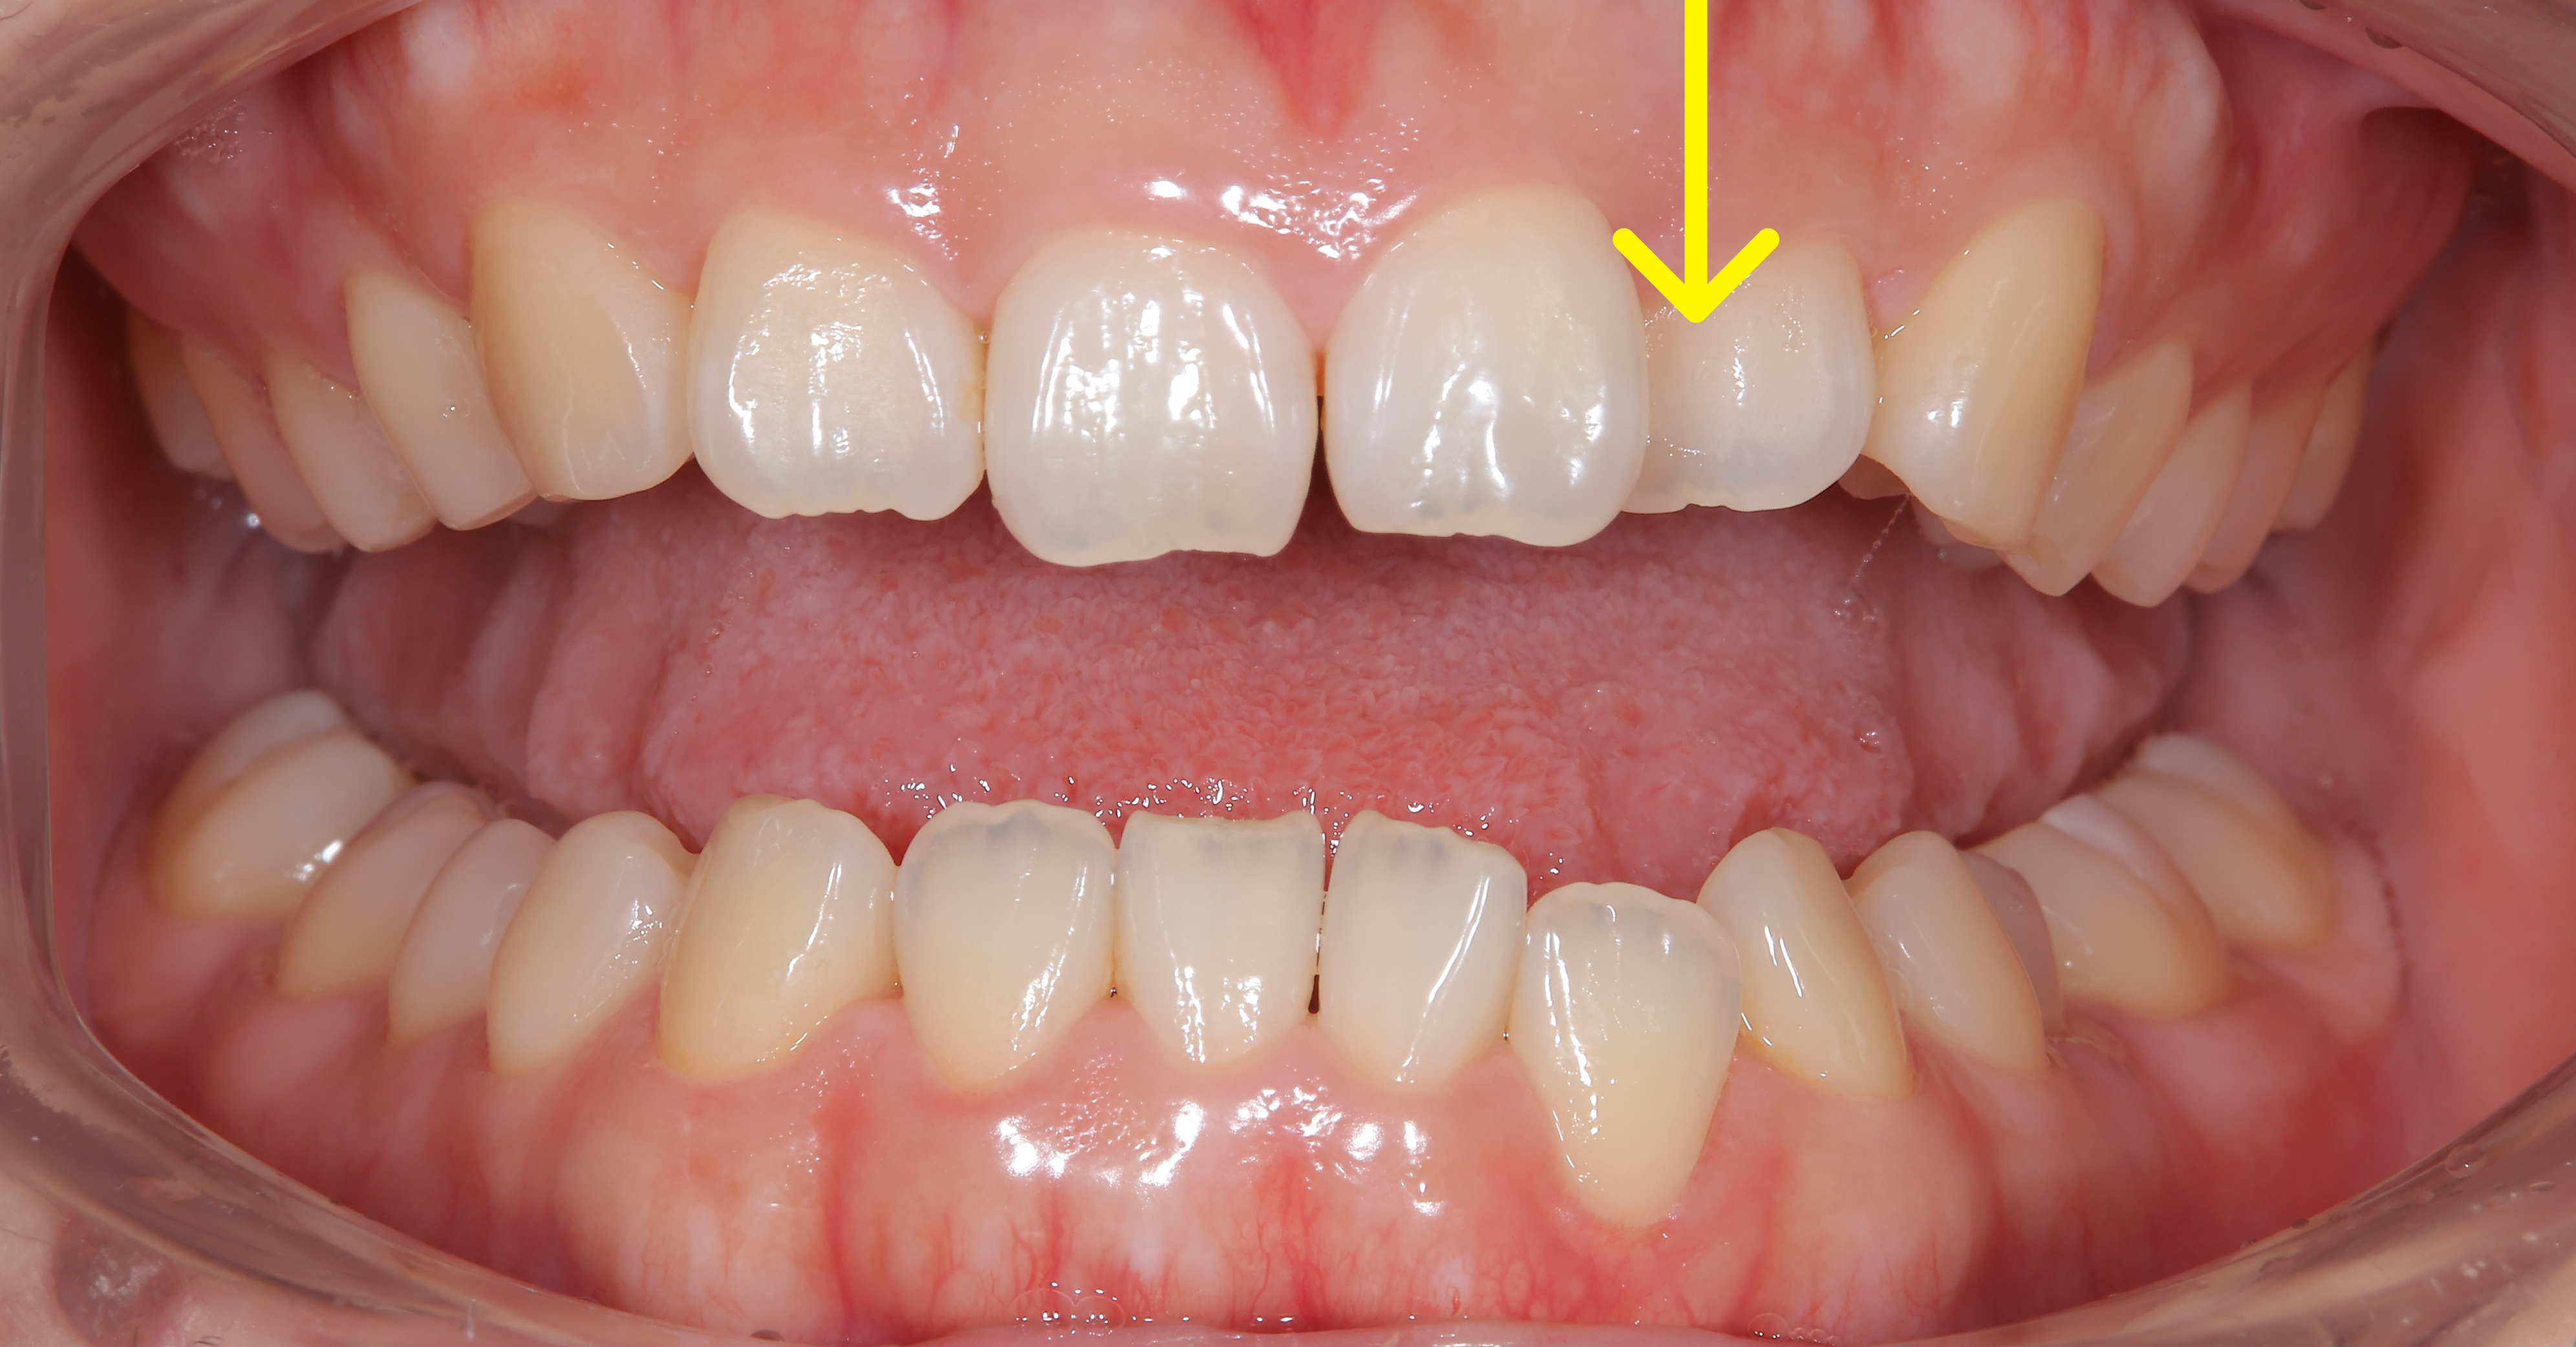

治療概要:矢印の歯は反対咬合(上の歯より下の歯の方が前に出ている)になっています。また、この方も過蓋咬合で下の前歯がほとんど見えません。

奥歯の噛み合わせはほとんど問題なく、マウスピース矯正を提案し矯正スタートしました。マウスピース矯正は食事中は外せたり、歯磨きもしっかりできるので良い治療法ですが、2番目の歯などあまり凹凸の少ない歯は動きが悪いことがあります。

下の写真が術前術後の比較です。下の前歯が見えるようになりました。上の前歯の傾きが変わるだけで口元の印象も変化します。